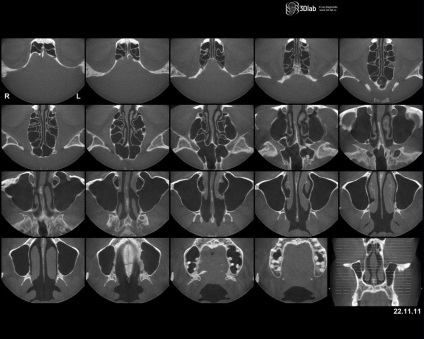

CT melléküregek - egy modern, informatív, non-invazív vizsgálati módszer a csont üregeiben ARCKOPONYA a koponya, amelyek levegővel vannak megtöltve, és kommunikálni az orrüregben.

A CT-vizsgálat lehetővé teszi, hogy megjelenítsék a nem csak a csontszerkezet, hanem a lágy szövetek és a tartalmát az orrmelléküregek, ha van ilyen.

Alkalmazásával kapott CT-képek a paranazális szinuszok rétegezett törlőkendőt szeletek vastagsága néhány mm és 1 cm. A vastagság a szeletek kézzel van beállítva a beállításokat a készülék, függően a betegség típusától, a jelenléte, ami arra utal, hogy azonosítsa a betegnek. Továbbá, a modern CT teszik lehetővé olyan háromdimenziós modell anatómiai struktúrák vizsgált régióban.

A vizsgálat során az orvos fekete-fehér kép a vizsgált területen, ahol egyes területeken megfelelnek az adott szövetek és anatómiai struktúrák az arc régióban a koponya.

Pillanatképek le van írva és megfejtette orvos gerenda diagnosztika. Jelek felismerésére patológia és a meglévő szövege a következtetést az orvos rendszerint 30-60 percig. A beteg megkapja a kezében kép tárolható bármilyen típusú lemez adathordozó vagy USB flash drive, vagy nyomtatott fólia vagy papír. A következtetés a betegnek adott papíron által hitelesített aláírás és pecsét a doktor.